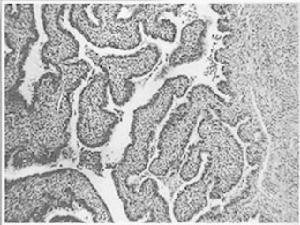

副伤寒甲、乙的病理变化大致与伤寒相同,肠出血或穿孔少出现,但胃肠炎型患者的肠道病变显著而广泛,且多侵及结肠。副伤寒丙的肠道病变不显著,肠壁可无溃疡形成,但常引起化脓症。败血症副伤寒常有骨、关节、脑膜、心包、软组织等处化脓性迁延性病灶。